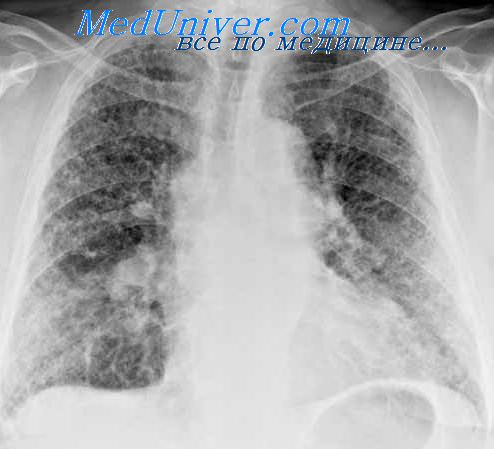

Большое дифференциально-диагностическое значение при постановке диагноза туберкулемы или рака имеет рентгенологическое исследование. Тень раковой опухоли более интенсивна, очертания ее менее резкие, волнистые, бугристые, тяжистые.

Иногда определяется так называемая вырезка — углубление в области вхождения в опухоль сосудисто-бронхиального пучка. В отличие от туберкулемы, в которой можно увидеть плотные обызвествленные включения, тень опухоли однородная или многоузловая.

Полости в раковом узле могут быть и мелкие, и более крупные, неправильной формы, с толстой стенкой. При туберкулезе полость начинает формироваться в периферических отделах, и только в дальнейшем происходят распад всей туберкулемы и образование тонкостенной полости.

В корне легкого у больного раком могут быть обнаружены метастазы опухоли, у больного с туберкулемой — кальцинированные лимфатические узлы.

По мере прогрессирования болезни выявляются некоторые общие признаки: кашель, кровохарканье, одышка, лихорадка, утомляемость, похудание, одинаковые физические изменения, ускоренная РОЭ, увеличение уровня глобулинов в сыворотке крови. Но основной причиной диагностических затруднений в этих случаях является довольно сходная рентгенологическая картина туберкуломы и шаровидного периферического рака.

Некоторым дифференциально-диагностическим подспорьем в ряде случаев является установление локализации патологической тени; периферический рак чаще располагается в 3, 4, 5-м сегментах, туберкулемы – в 1, 2, 6-м сегментах (рис. 75–77).

При туберкулемах в легочной ткани в близлежащих или более отдаленных бронхолегочных сегментах того же или другого легкого часто определяют другие изменения туберкулезного характера: плотные или обызвествленные очаги, фиброзные тени, плевральные изменения. При периферическом раке легкого, как правило, наблюдается прогрессирующий рост опухолевого узла.